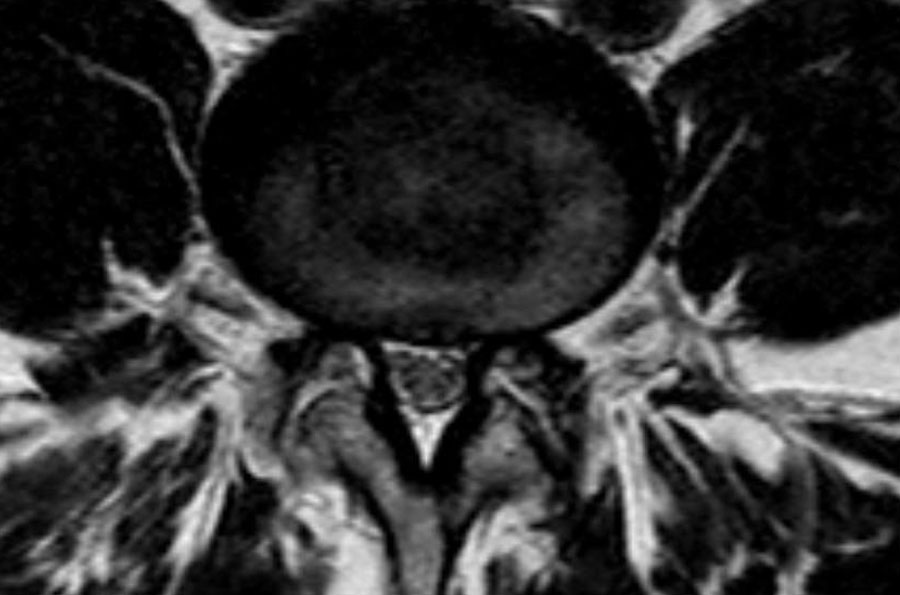

Hình ảnh chuỗi xung T1W mặt phẳng đứng dọc cho thấy một cấu trúc giảm tín hiệu rất thấp tại mức L4L5 (mũi tên) và tại mức L5S1.

Tiếp tục xem các hình ảnh chuỗi xung T2W.

Trên chuỗi xung T2W, cường độ tín hiệu cũng rất thấp.

Chụp CT được thực hiện để xác định liệu đây có phải là đĩa đệm thoát vị bị vôi hóa hay một xảo ảnh nào đó.

Tiếp tục xem các hình ảnh CT.

Tín hiệu thấp cuối cùng được giải thích là do hiện tượng chân không (vacuum phenomenon) gây ra bởi khí nitơ trong đĩa đệm thoát vị tại cả mức L4L5 (mũi tên đỏ) và mức L5S1 (mũi tên xanh dương).